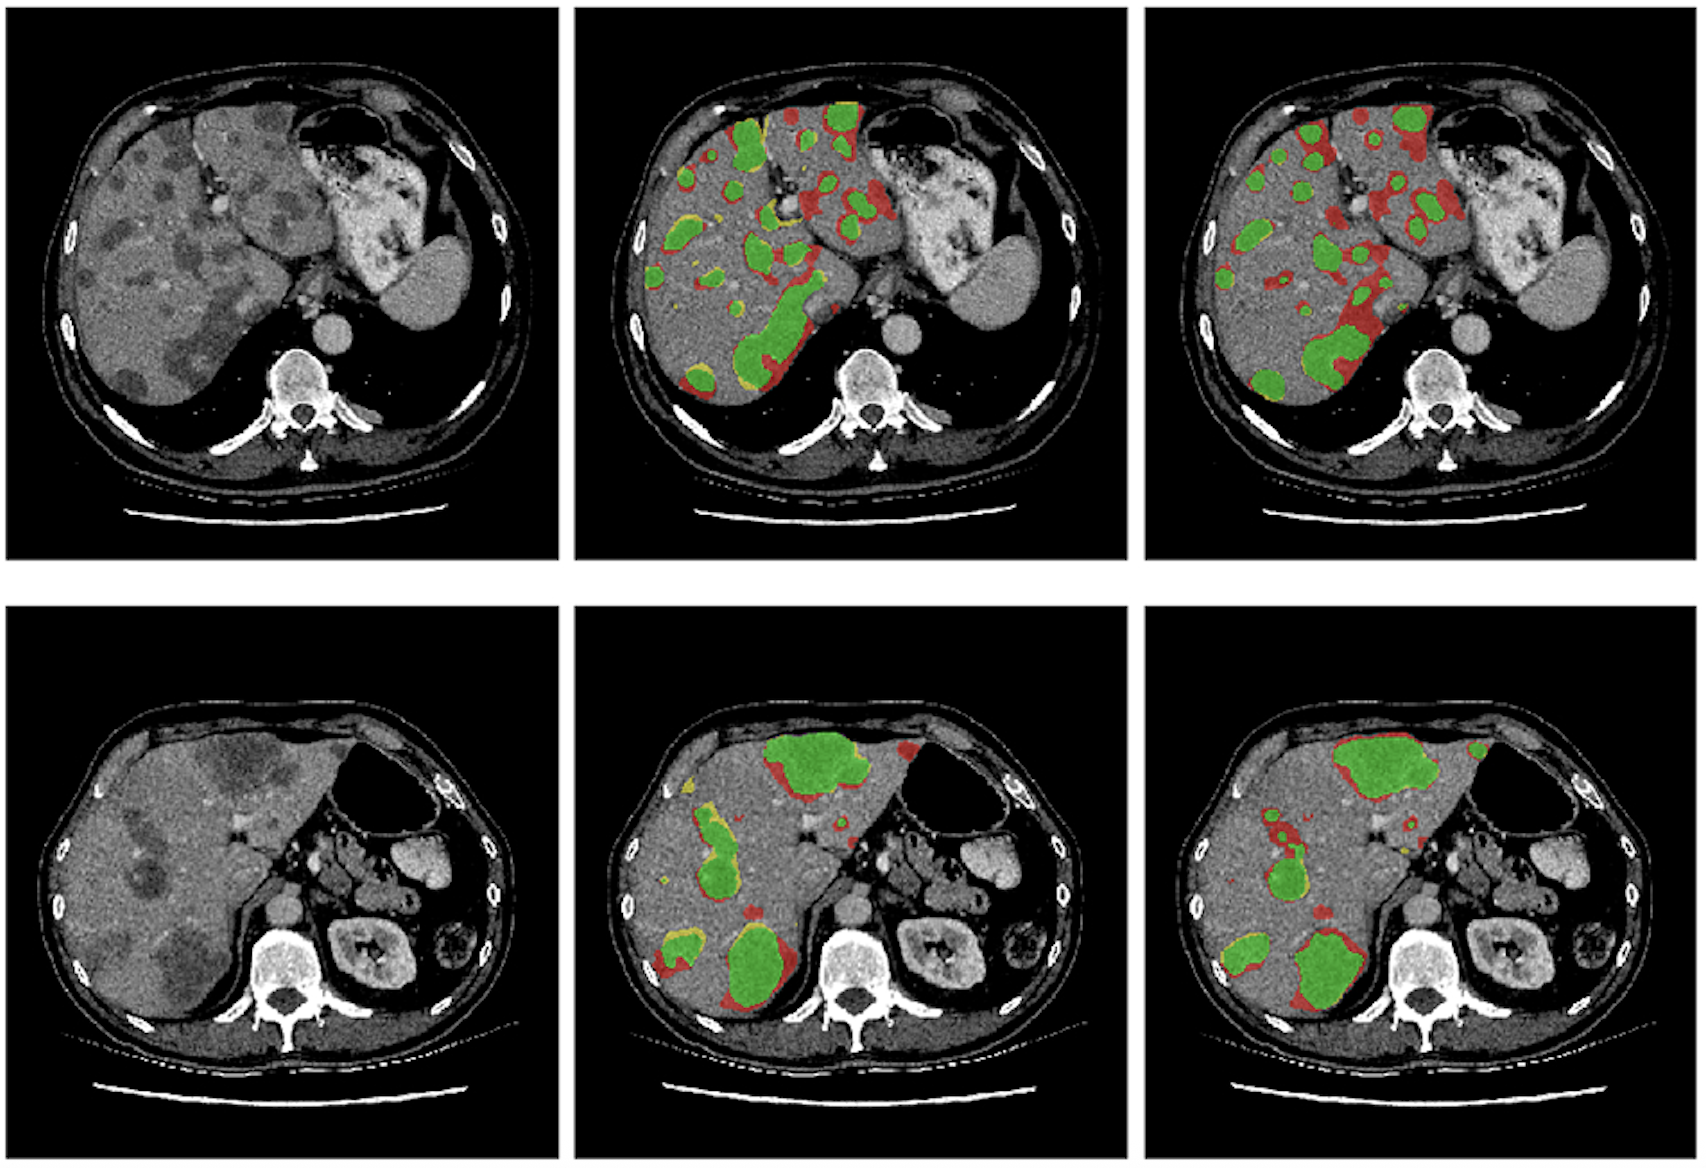

The paper proposes a deep learning method that improves biomarker prediction and localization using only biomarker values, without requiring segmentation masks.